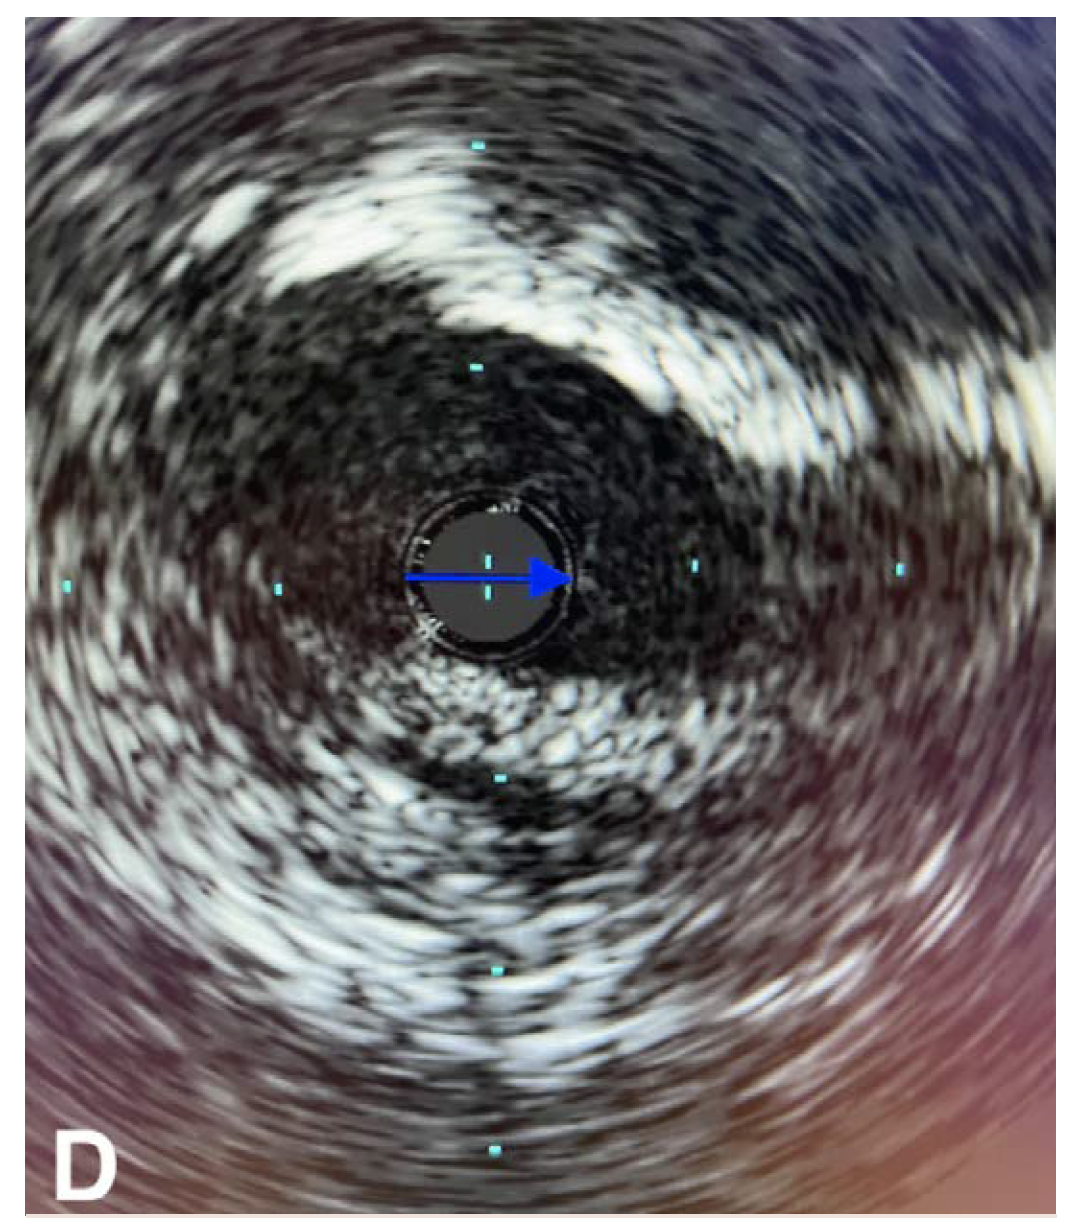

The patient underwent an initial catheter-directed diagnostic angiogram that revealed a 99% stenosis of the left CFA. The lesion was successfully transversed, and a 7 Fr 45-cm sheath was placed in the left external iliac artery. Intravascular ultrasound (IVUS) was performed over a 0.014" wire (Figure 1A), which demonstrated near occlusion of the CFA with heavy calcium burden. An 8-mm x 60-mm Shockwave balloon was then inflated to 4 atm, and 10 cycles were used to treat the CFA and proximal superficial femoral artery (Figure 1B). Completion angiogram showed an excellent result, with complete resolution of the calcific disease and no residual stenosis (Figure 1C). IVUS was performed at the end, which showed more than 80% luminal expansion after IVL treatment (Figure 1D). The patient was awakened from monitored anesthesia care and discharged from the postanesthesia care unit to home the same day.